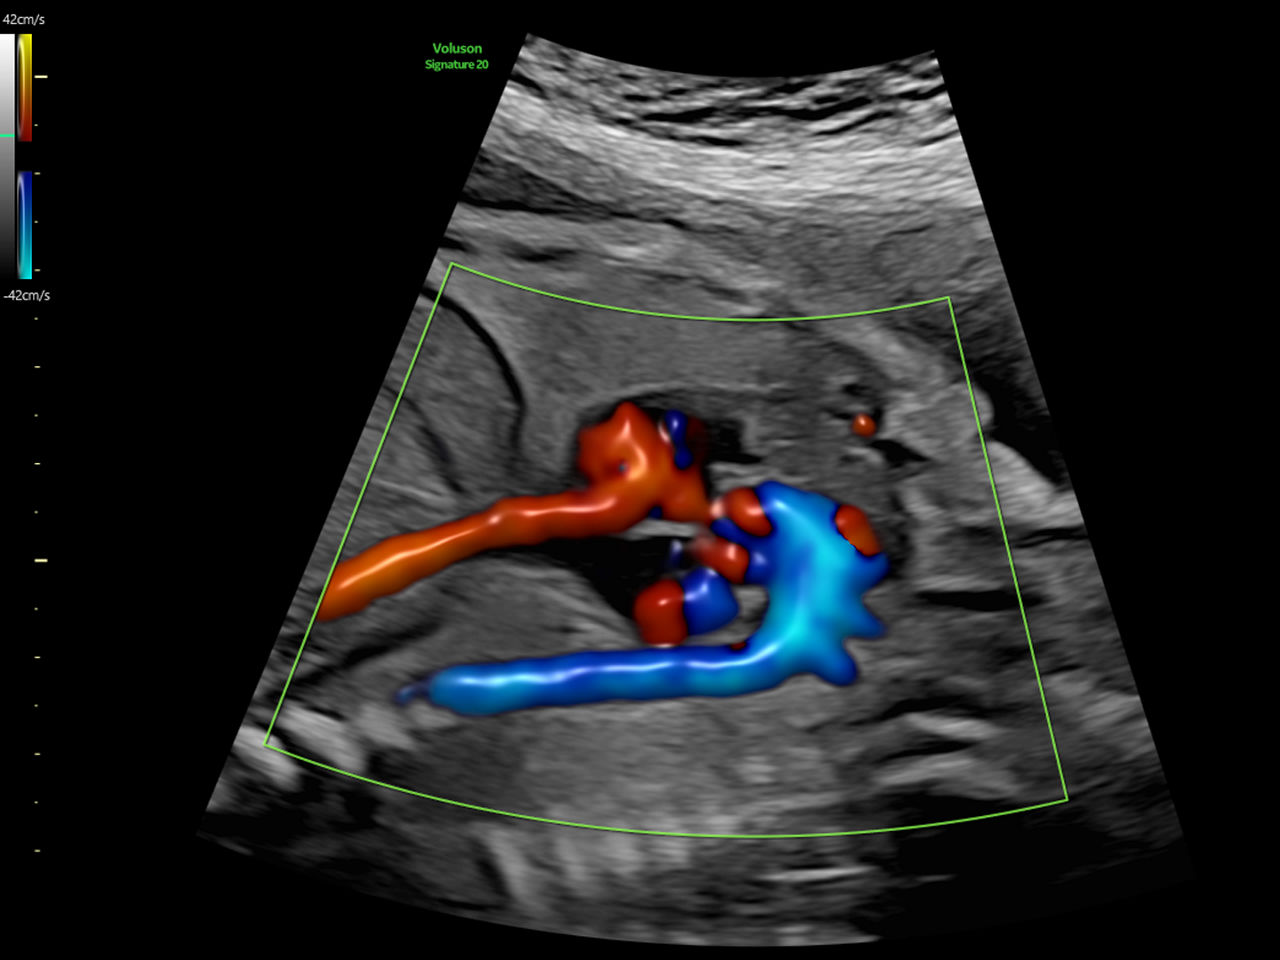

Fast, easy 3D-like blood flow visualization

Next level color Doppler that delivers exceptional sensitivity for easy, fast visualization of blood flow, displaying a 3D like appearance as seen in this 27-week fetal heart.